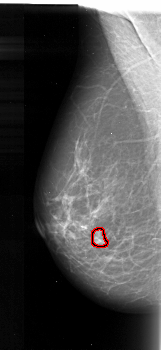

A_1102_1.RIGHT_CC

RIGHT_CC LINES 4516 PIXELS_PER_LINE 2146 BITS_PER_PIXEL 16 RESOLUTION 42 NON_OVERLAY

FILE: A_1102_1.LEFT_CC.OVERLAY

TOTAL_ABNORMALITIES 1

ABNORMALITY 1

LESION_TYPE MASS SHAPE IRREGULAR MARGINS ILL_DEFINED

ASSESSMENT 4

SUBTLETY 3

PATHOLOGY MALIGNANT

TOTAL_OUTLINES 1

BOUNDARY